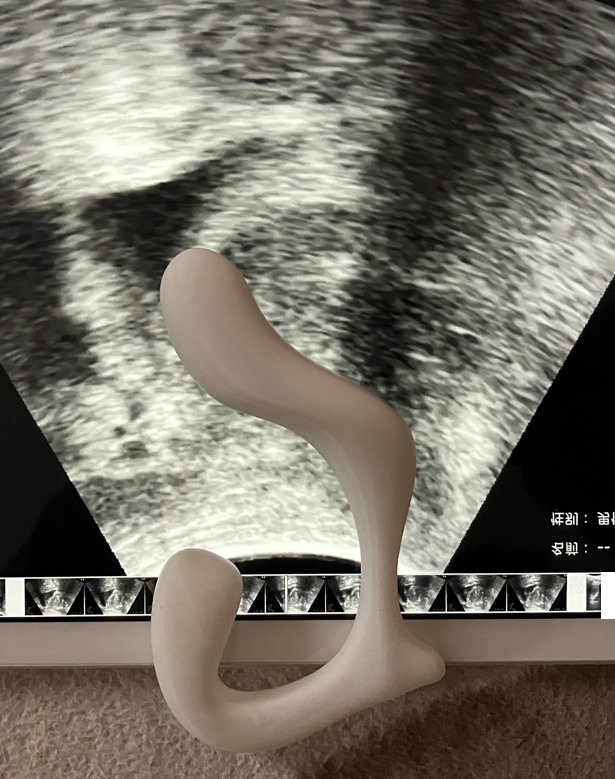

そこで、3Dプリンタでこういう形のものを作ってみました。

シントライデントやEX2よりヘッドが前に突き出ているようにしました。

前立腺との位置関係がこのようになると思います。

使ってみたところ、入れてすぐに精液が漏れ出てしたたり落ちました。